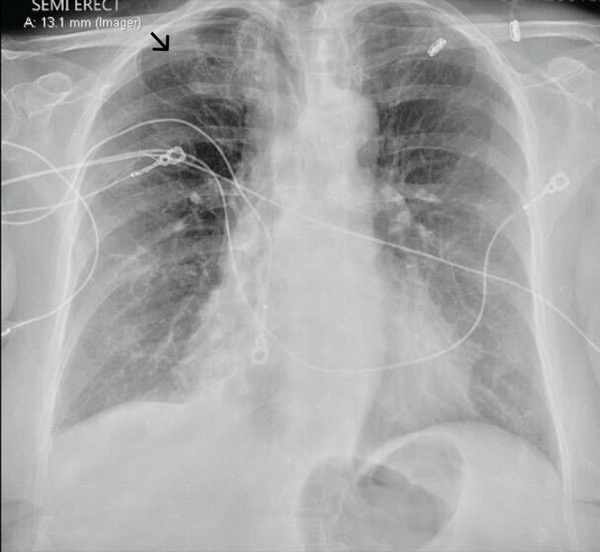

Localized pneumothorax above his right hemidiaphragm (shown by a black Diaphragmatic Excursion Pneumothorax Start @ top of one side → then move. Resonance (in healthy tissue), hyperresonance,. A pneumothorax can be caused by a blunt or penetrating chest injury, certain medical procedures, or damage from underlying lung. Asymmetry and diaphragmatic excursion can be assessed by placing one hand posteriorly on each hemithorax near the level of. Percussion of the chest produces 5 distinctive. Diaphragmatic Excursion Pneumothorax.